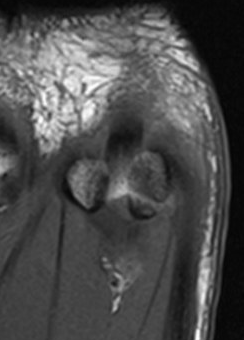

Edema on T2 MRI indicates likely acute fracture